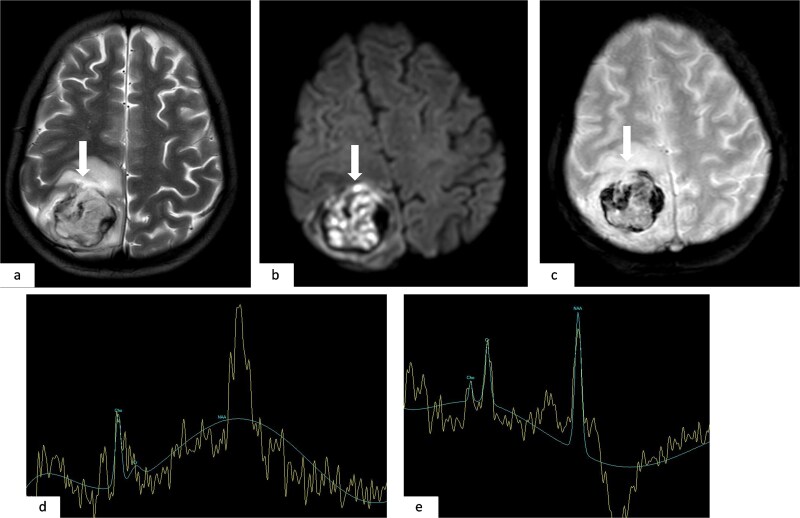

骨肉瘤是儿童和青少年中最常见的恶性骨肿瘤,以长骨为主,常发生肺转移。脑转移是罕见的,发生在1.8%至5.6%的病例中,出血性转移非常罕见,文献中只有少数病例记录。我们报告的情况下,一个16岁的女孩谁提出急性头痛和癫痫发作。影像显示出出血性脑和肺转移,活检证实为原发性股骨骨肉瘤。本病例是一种罕见的骨肉瘤,并突出了其侵袭性转移行为。

Osteosarcoma is the most common malignant bone tumor in children and adolescents, with a predilection for long bones and frequent pulmonary metastases. Brain metastases are rare, occurring in 1.8% to 5.6% of cases, and hemorrhagic ones are exceptionally uncommon, with only a few cases documented in the literature. We report the case of a 16-year-old girl who presented with acute headache and seizures. Imaging revealed hemorrhagic brain and pulmonary metastases, and biopsy confirmed a primary femoral osteosarcoma. This case represents an exceptionally rare presentation of osteosarcoma and highlights its aggressive metastatic behavior.